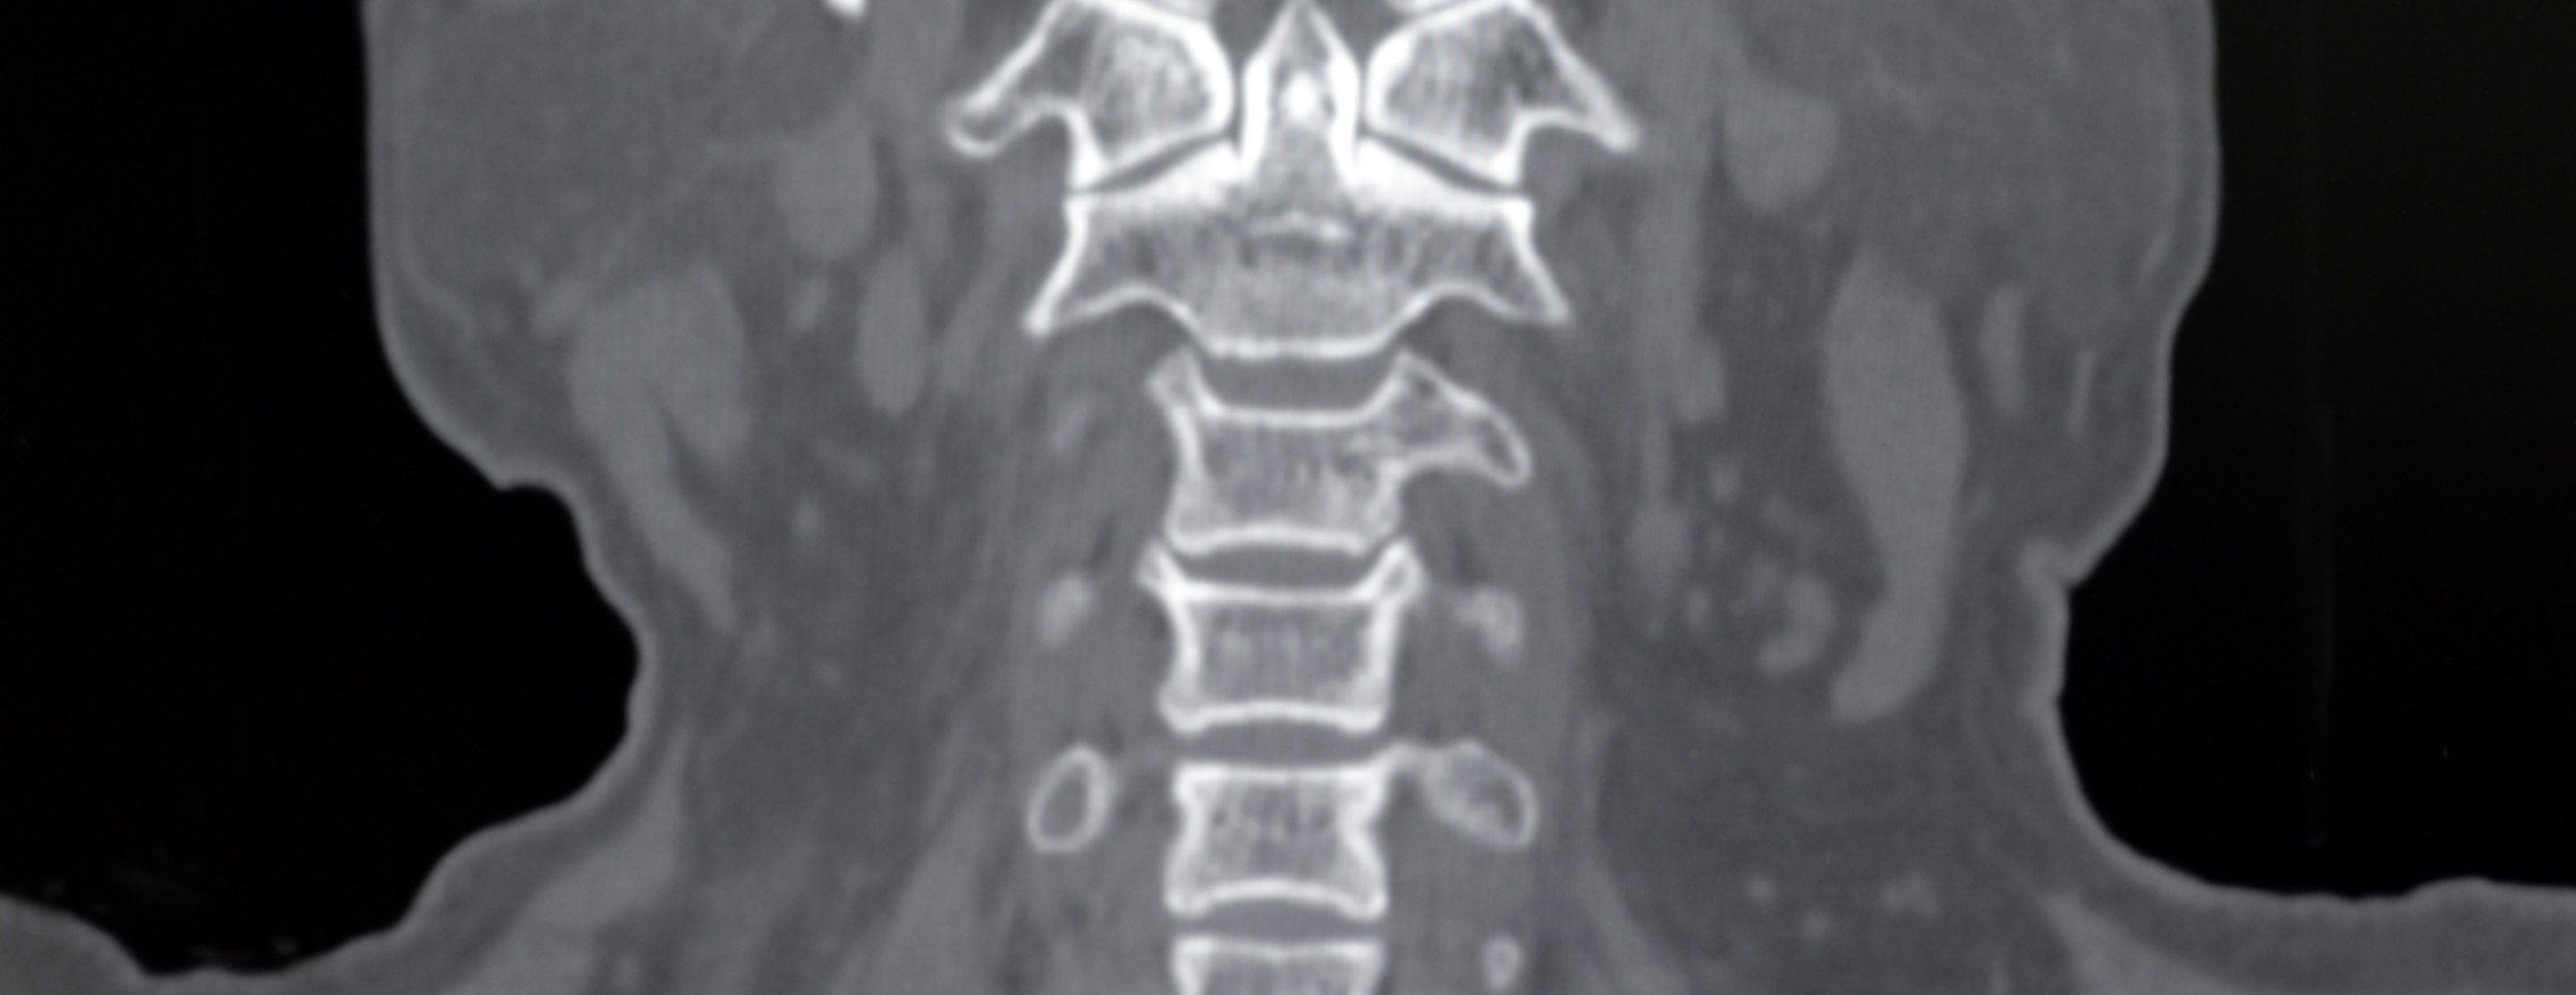

Cervical spine CT scan

A computed tomography (CT) scan of the cervical spine makes cross-sectional pictures of the neck. It uses x-rays to create the images.

A computer creates separate images of the body area, called slices. These images can be stored, viewed on a monitor, or printed on film. Three-dimensional models of the cervical spine can be created by adding the slices together.